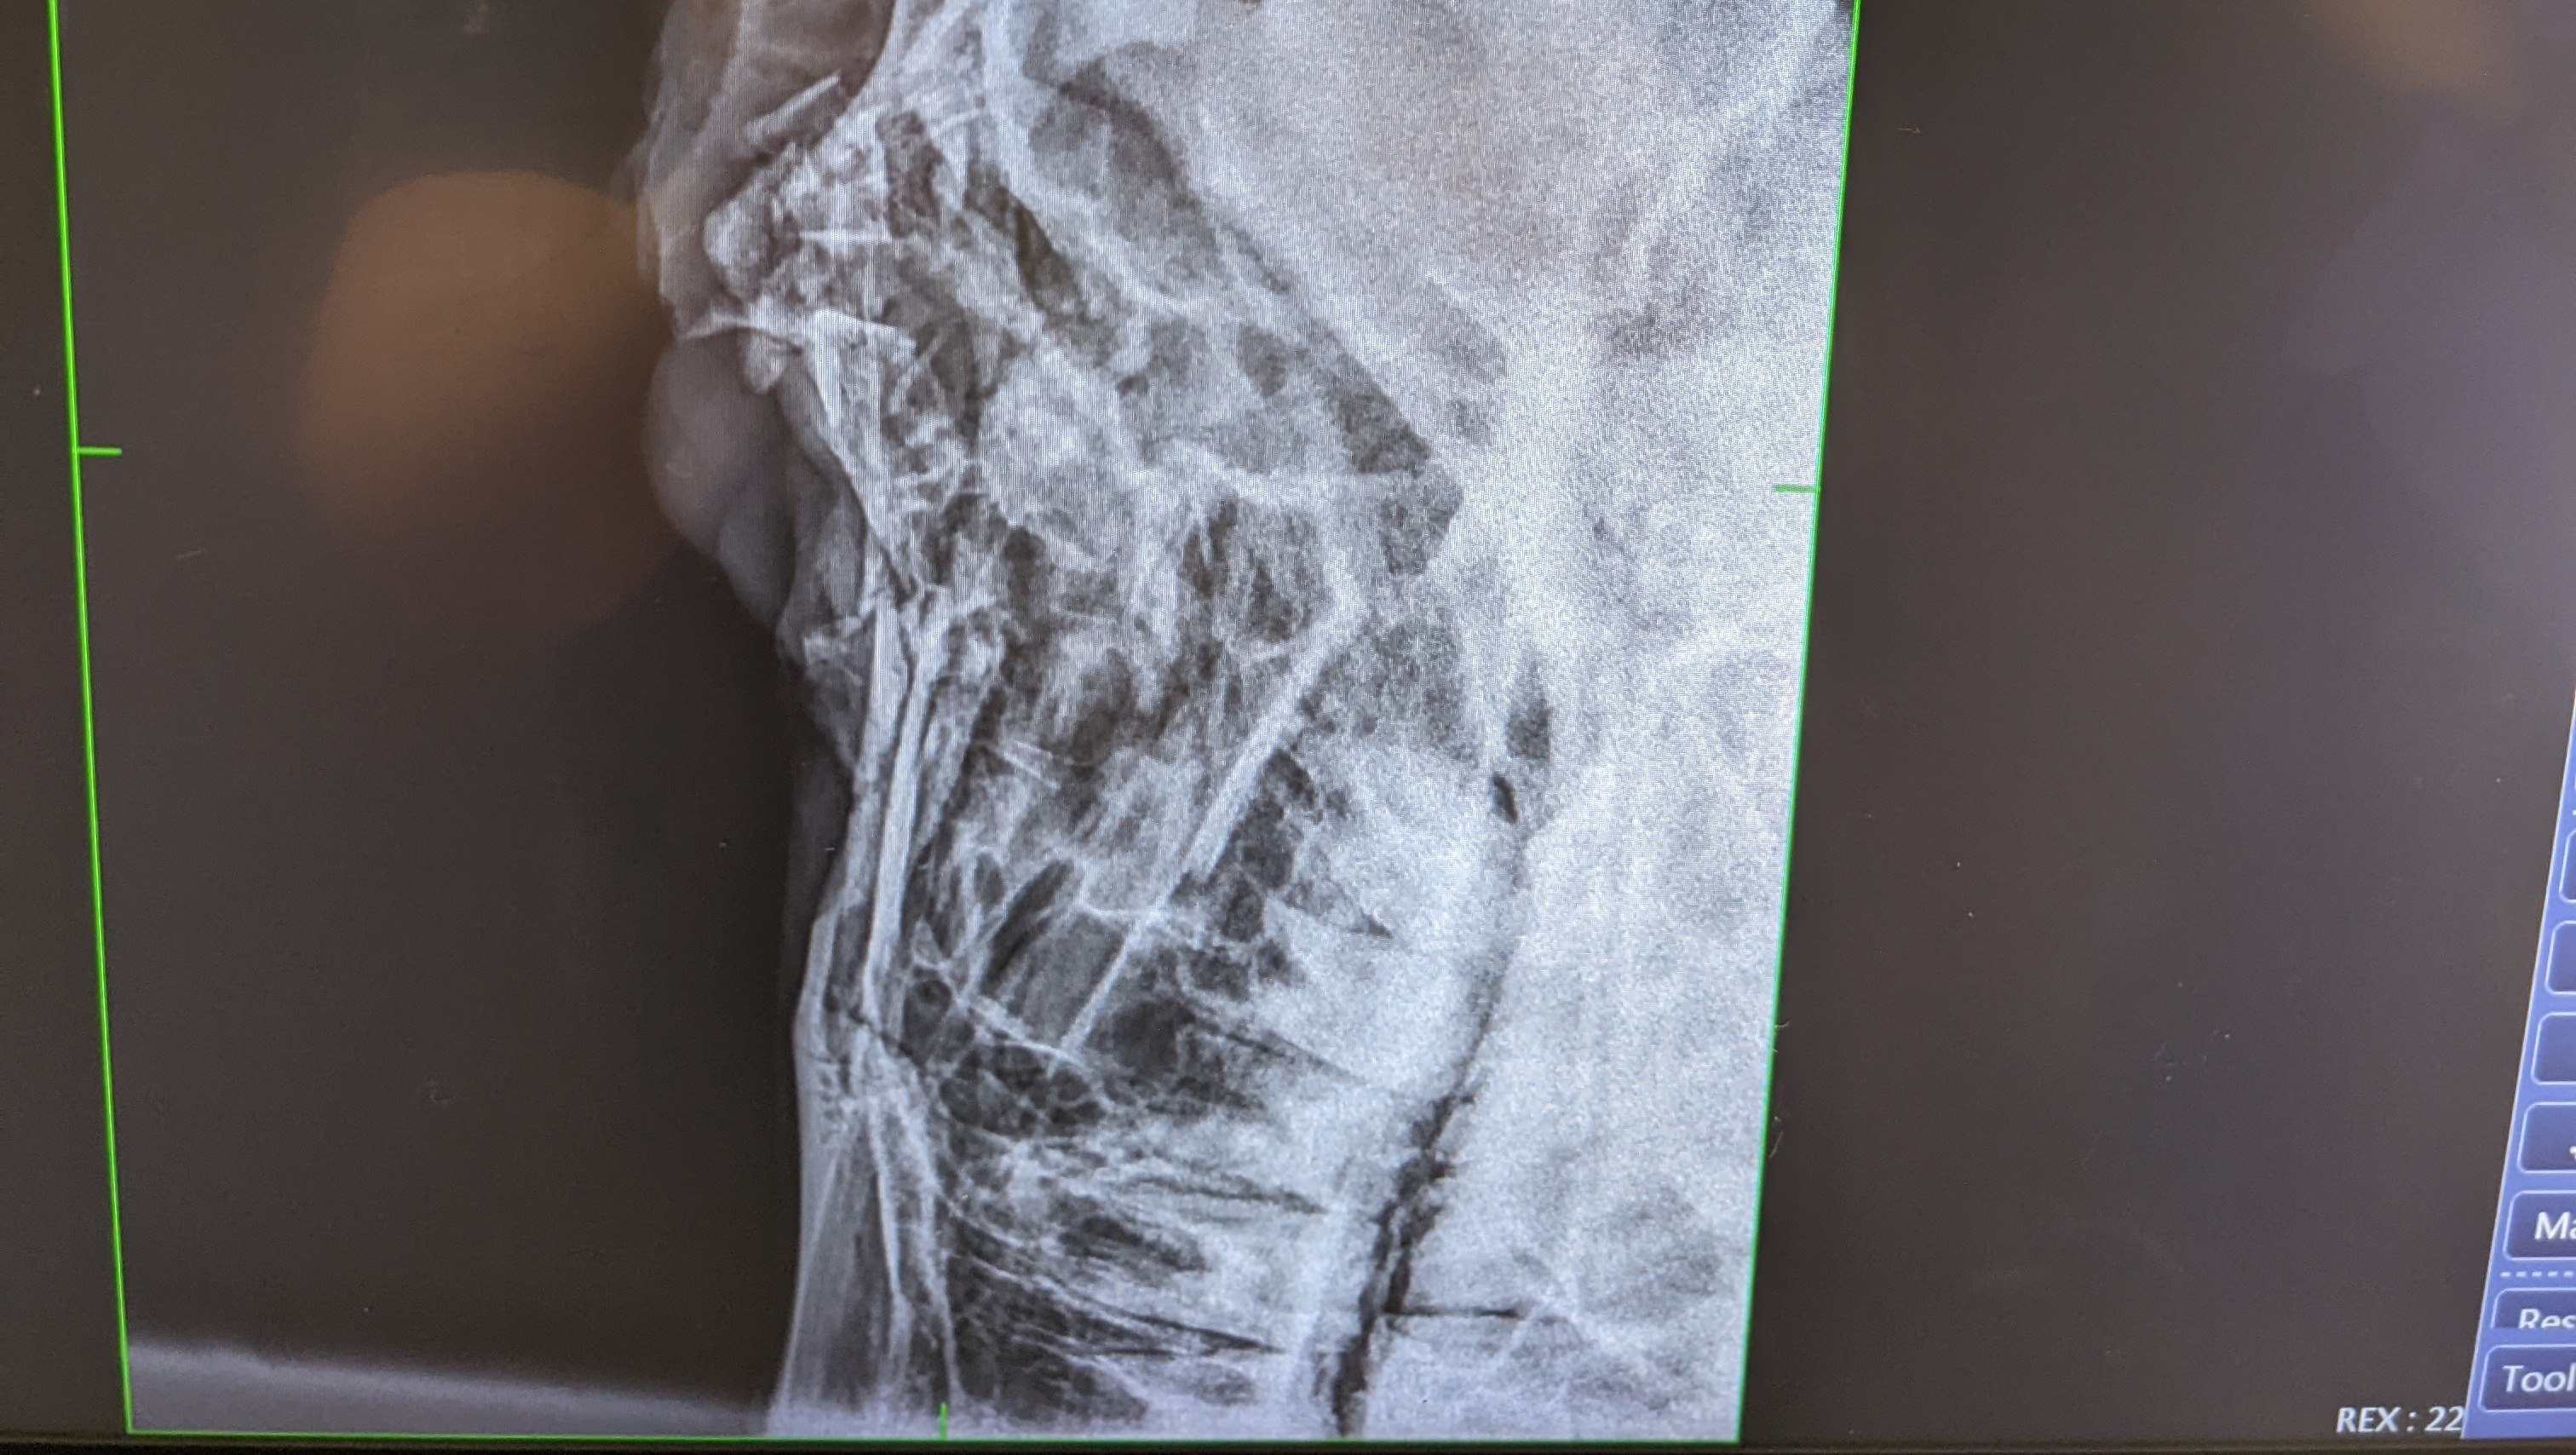

On 6/18/22, near 11:30 PM, a faulty gate lock let him and other horses out of a wooded acre+ paddock. The horses crossed and ran down the insanely (almost interstate-worthy) busy highway. The other horses made it to safety and were caught. King did not. It was a two-hour search before he was found with his skull partially crushed from being hit by a vehicle. The driver left, but the debris was left behind.

King must have his right eye removed and have reconstruction surgery. After surgery, board, and medication it will likely cost around $2000...But that is an early estimate that could change depending on what happens.